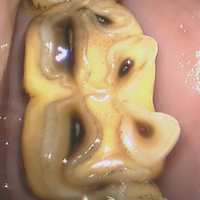

Net zoals bij mensen kunnen tanden bij paarden behouden worden wanneer het probleem vroeg genoeg waargenomen wordt. Een regelmatig mondonderzoek is dan ook de boodschap! In sommige gevallen kan er een preventieve behandeling uitgevoerd worden om te voorkomen dat een tand breekt ten gevolge van tandbederf (cariës). Hierbij wordt het “slechte deel van de tand” verwijderd met behulp van boortjes (dezelfde als diegene die dat akelige geluid maken bij je eigen tandarts).

Na het desinfecteren van de tand wordt er dan een vulling geplaatst om het slechte tandweefsel te vervangen. Niet alleen preventief, maar ook bij tandontstekingen kan een tand-sparende behandeling uitgevoerd worden. Een dergelijke wortelkanaalbehandeling (endodontie) is wel iets gecompliceerder dan bij de mens en in veel gevallen dient de behandeling in 2 of meerdere keren uitgevoerd te worden. Dit heeft wel als grote voordeel dat het paard zijn tand kan behouden en mogelijke complicaties na een tandextractie niet kunnen optreden.